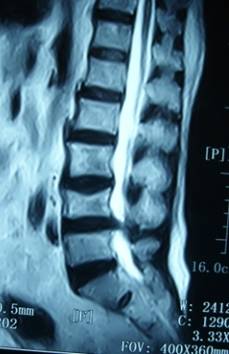

2. 患者董某,女,70岁,因“腰部疼痛并右下肢疼痛、麻木1年余,加重10天”入院。入院前曾多次行针灸、理疗、骶管封闭等治疗,经治疗后病情复发。入院见患者腰痛并右下肢疼痛,双足麻木,间歇性跛行,跛行距离约50米。查:直腿抬高试验右30°阳性,右踇背伸肌力、腓骨长短肌肌力Ⅲ级,双小腿外侧、足背皮肤感觉减退,右侧为甚。入院后诊断为腰椎间盘突出症。患者既往患高血压、冠心病、慢性胆囊炎、胆结石病史,形体肥胖。入院后完善检查,明确诊断,请相关科室会诊后认为手术风险大且患者形体肥胖,为手术增加难度,势必延长手术时间,增加手术风险。经科室讨论后行经皮椎间孔镜下髓核摘除,手术麻醉方式为局麻。入院后第三日手术,经椎间孔入路椎间孔镜下髓核摘除椎管扩大成形术。手术顺利,术中无出血,手术时间约1小时。术中可与患者交流。术后患者即可感右下肢无疼痛,第二天佩戴腰围下地活动后双下肢无不适。术后第三天出院,术后第三天复查腰椎MRI示突出髓核已摘除,神经根无受压。术后随访三月,患者目前病情恢复良好,无下肢疼痛。

术前患者腰椎MRI